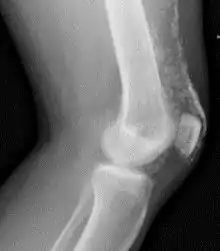

Calcification from dermatomyositis

X-Ray of the knee in a person with dermatomyositis.

Magnetic resonance imaging may be useful to guide muscle biopsy and to investigate involvement of internal organs;[14] X-ray may be used to investigate joint involvement and calcifications.[15]